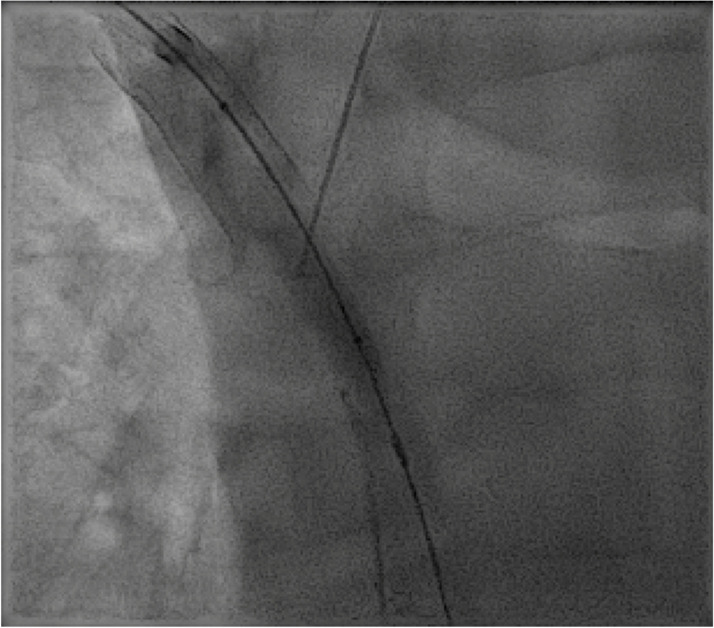

Axillo-caval extra-anatomic venous bypass creation via direct percutaneous puncture of the superior vena cava.

Abstract Image